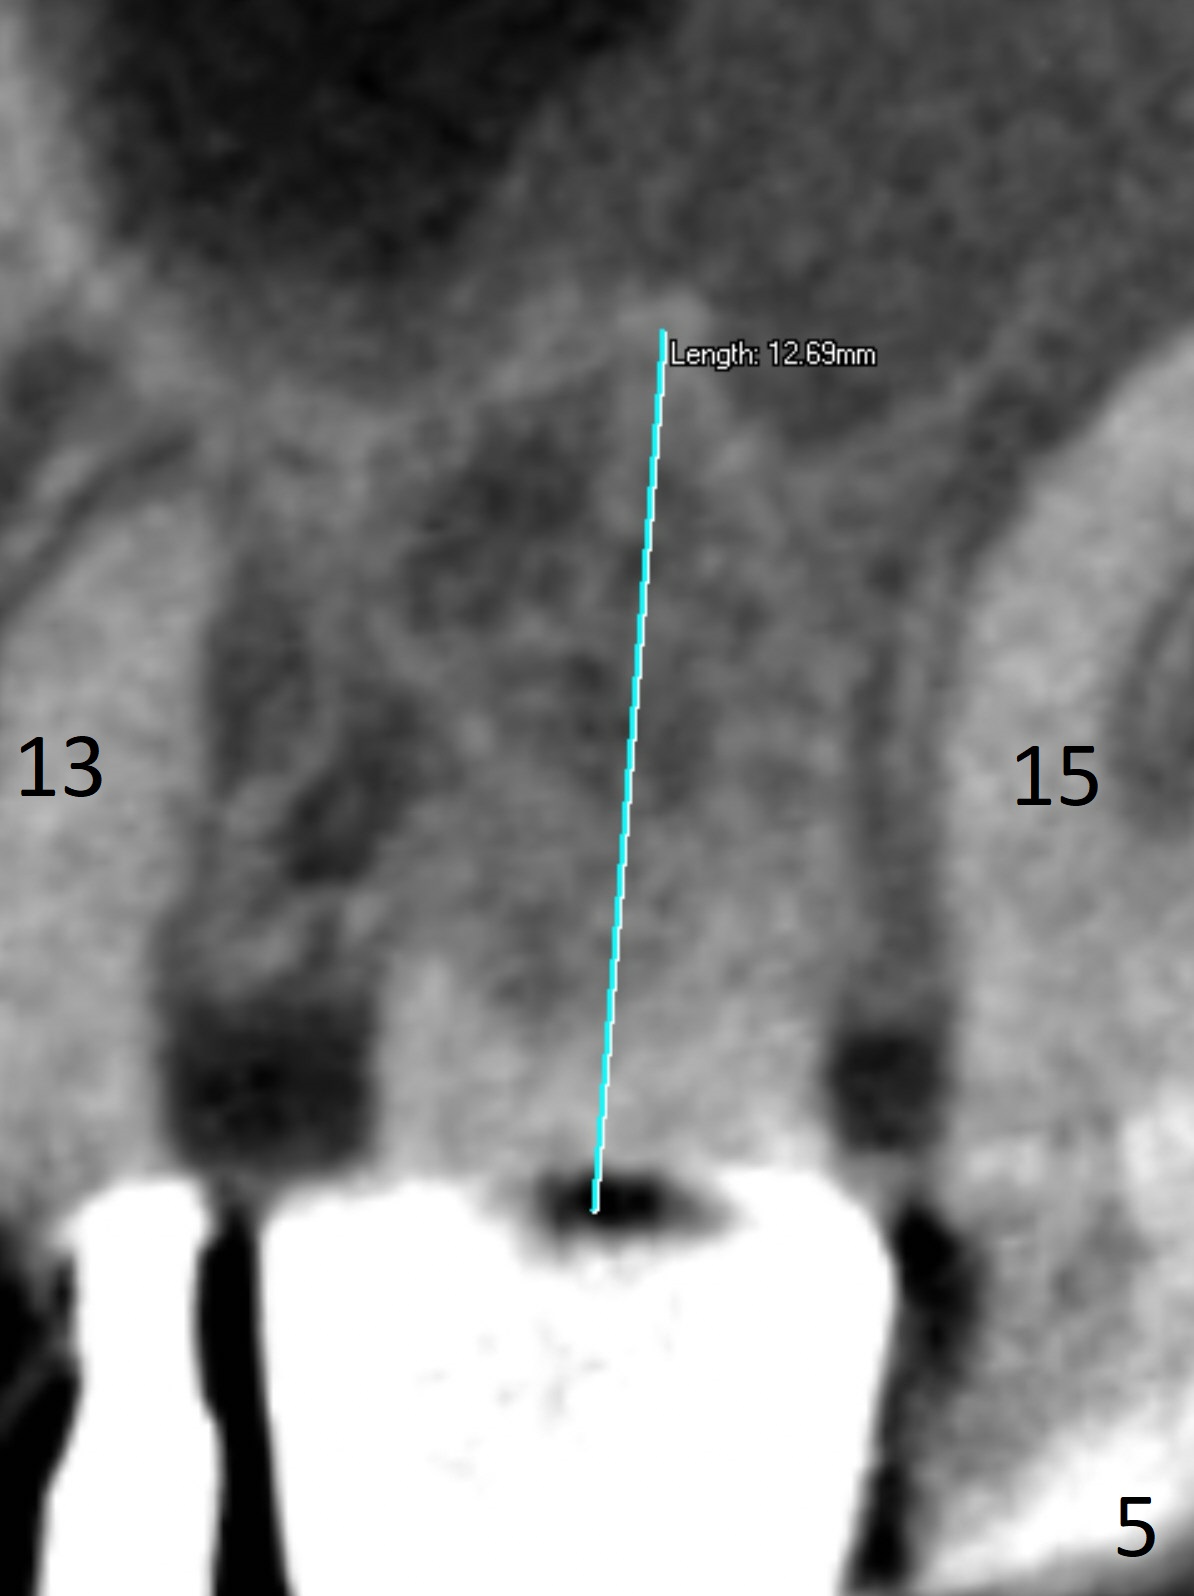

Soft Tissue Landmark for Osteotomy Depth

A 70-year-old woman fractures the crown at #14 (Fig.1). A 5x11 mm implant will be placed at the septum (Fig.2). Osteotomy depth can be determined using bony (Fig.3 with stopper) or gingival (Fig.4,5 with vision) landmark. The CT was taken 5 years earlier. Sagittal (Fig.6) and axial (Fig.7) sections confirm suitability of the 5x11 mm implant for the site. Prepare surgical handpiece for sectioning the tooth for extraction. After drills, use Magic Expanders for sinus lift. Place Vanilla Graft prior to dummy implant(s). A bone-level implant crown may be easier to be repaired if the proximal contact is not ideal.